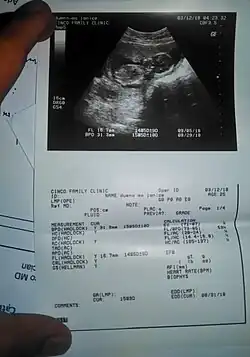

Obstetrical sonography was originally developed in the late 1950s and 1960s by Sir Ian Donald[20][21] and is commonly used during pregnancy to check the development and presentation of the fetus. It can be used to identify many conditions that could be potentially harmful to the mother and/or baby possibly remaining undiagnosed or with delayed diagnosis in the absence of sonography. It is currently believed that the risk of delayed diagnosis is greater than the small risk, if any, associated with undergoing an ultrasound scan. However, its use for non-medical purposes such as fetal "keepsake" videos and photos is discouraged.[22]

Obstetric ultrasound is primarily used to:

• Date the pregnancy (gestational age)

• Confirm fetal viability

• Determine location of fetus, intrauterine vs ectopic

• Check the location of the placenta in relation to the cervix

• Check for the number of fetuses (multiple pregnancy)

• Check for major physical abnormalities.

• Assess fetal growth (for evidence of intrauterine growth restriction (IUGR))

• Check for fetal movement and heartbeat.

• Determine the sex of the baby